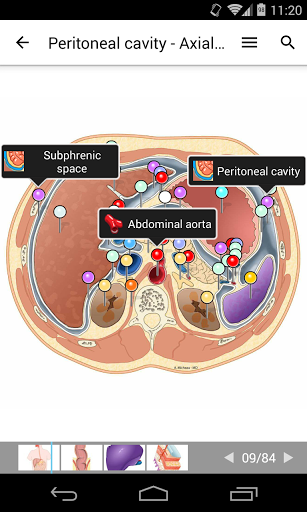

* وحدة جديدة للمستخدمين المتميزين: تشريح البطن والحوض لدى الأنثى على التصوير المقطعي المحوسب

بالإضافة إلى وحدتين تشريحيتين جديدتين:

-أطلس تشريح الغلاف (الجلد والشعر والغدد الجلدية)

-أطلس تشريح الحوض الذكري والجهاز التناسلي.

وحدات جديدة للمستخدمين المتميزين:

- التصوير بالرنين المغناطيسي

العادي لأرقام اليد - التصوير بالرنين المغناطيسي العادي للإبهام

وحدات جديدة لجميع المستخدمين:

-التشريح الجراحي لاستئصال باطنة الشريان السباتي